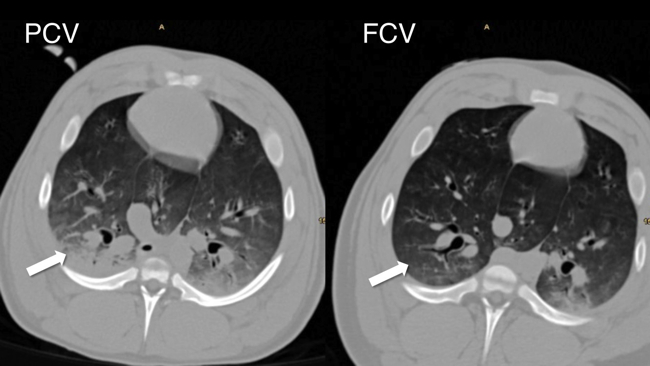

Our group investigates flow-controlled ventilation (FCV) as a novel ventilation method established to guarantee a continuous, constant and typically identical flow during inspiration and expiration. Additionally, the constant flow coupled with direct intratracheal pressure measurement allows accurate evaluation of dynamic compliance and adjustment of ventilation settings accordingly. Our first experimental pilot study demonstrated more efficient gas exchange and improved oxygenation as well as less atelectasis in individualised FCV compared with pressure-controlled ventilation (PCV) at the best standard of care during long term ventilation. Similar results were observed in an experimental model of single lung ventilation and in an experimental model of acute respiratory distress syndrome. Two clinical ventilation studies are currently being conducted in patients undergoing cardiac surgery and thoracic surgery with single lung ventilation, comparing individualised FCV with standard-of-care PCV.

- Spraider, P.; Martini, J.; Abram, J.; Putzer, G.; Glodny, B.; Hell, T.; Barnes, T.; Enk, D.: Individualized flow-controlled ventilation compared to best clinical practice pressure-controlled ventilation: a prospective randomized porcine study. CRITICAL CARE. 2020; 24(1): 662.

- Enk, D.; Spraider, P.; Abram, J.; Barnes, T.: Pressure Measurements in Flow-Controlled Ventilation. CIRTICAL CARE MEDICINE. 2020; 48(12): e1359-e1360.